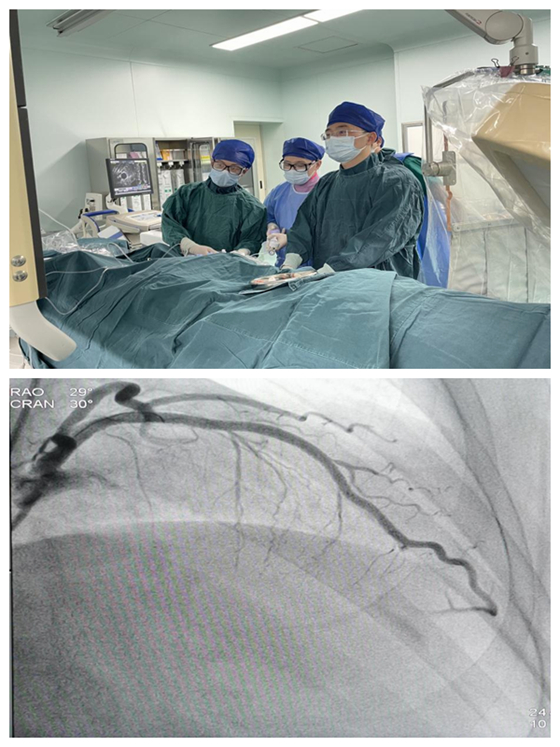

完善术前准备后,在心血管内科主任彭道地指导下,杨国栋、龚辉、彭双携手介入团队,于前降支近中段使用乐普3.0×12mm冲击波球囊以4atm扩张,释放冲击波脉冲,共重复8个周期,然后植入3枚药物洗脱支架覆盖病变。术后复查造影示支架贴壁良好,支架内无狭窄,远端血流正常,手术顺利完成。没有出现并发症。

此例手术的成功及患者的康复,为我院心内科救治复杂冠脉病变患者积累丰富的经验,也将进一步为湘西北地区乃至全省全国的冠心病患者带来福音。